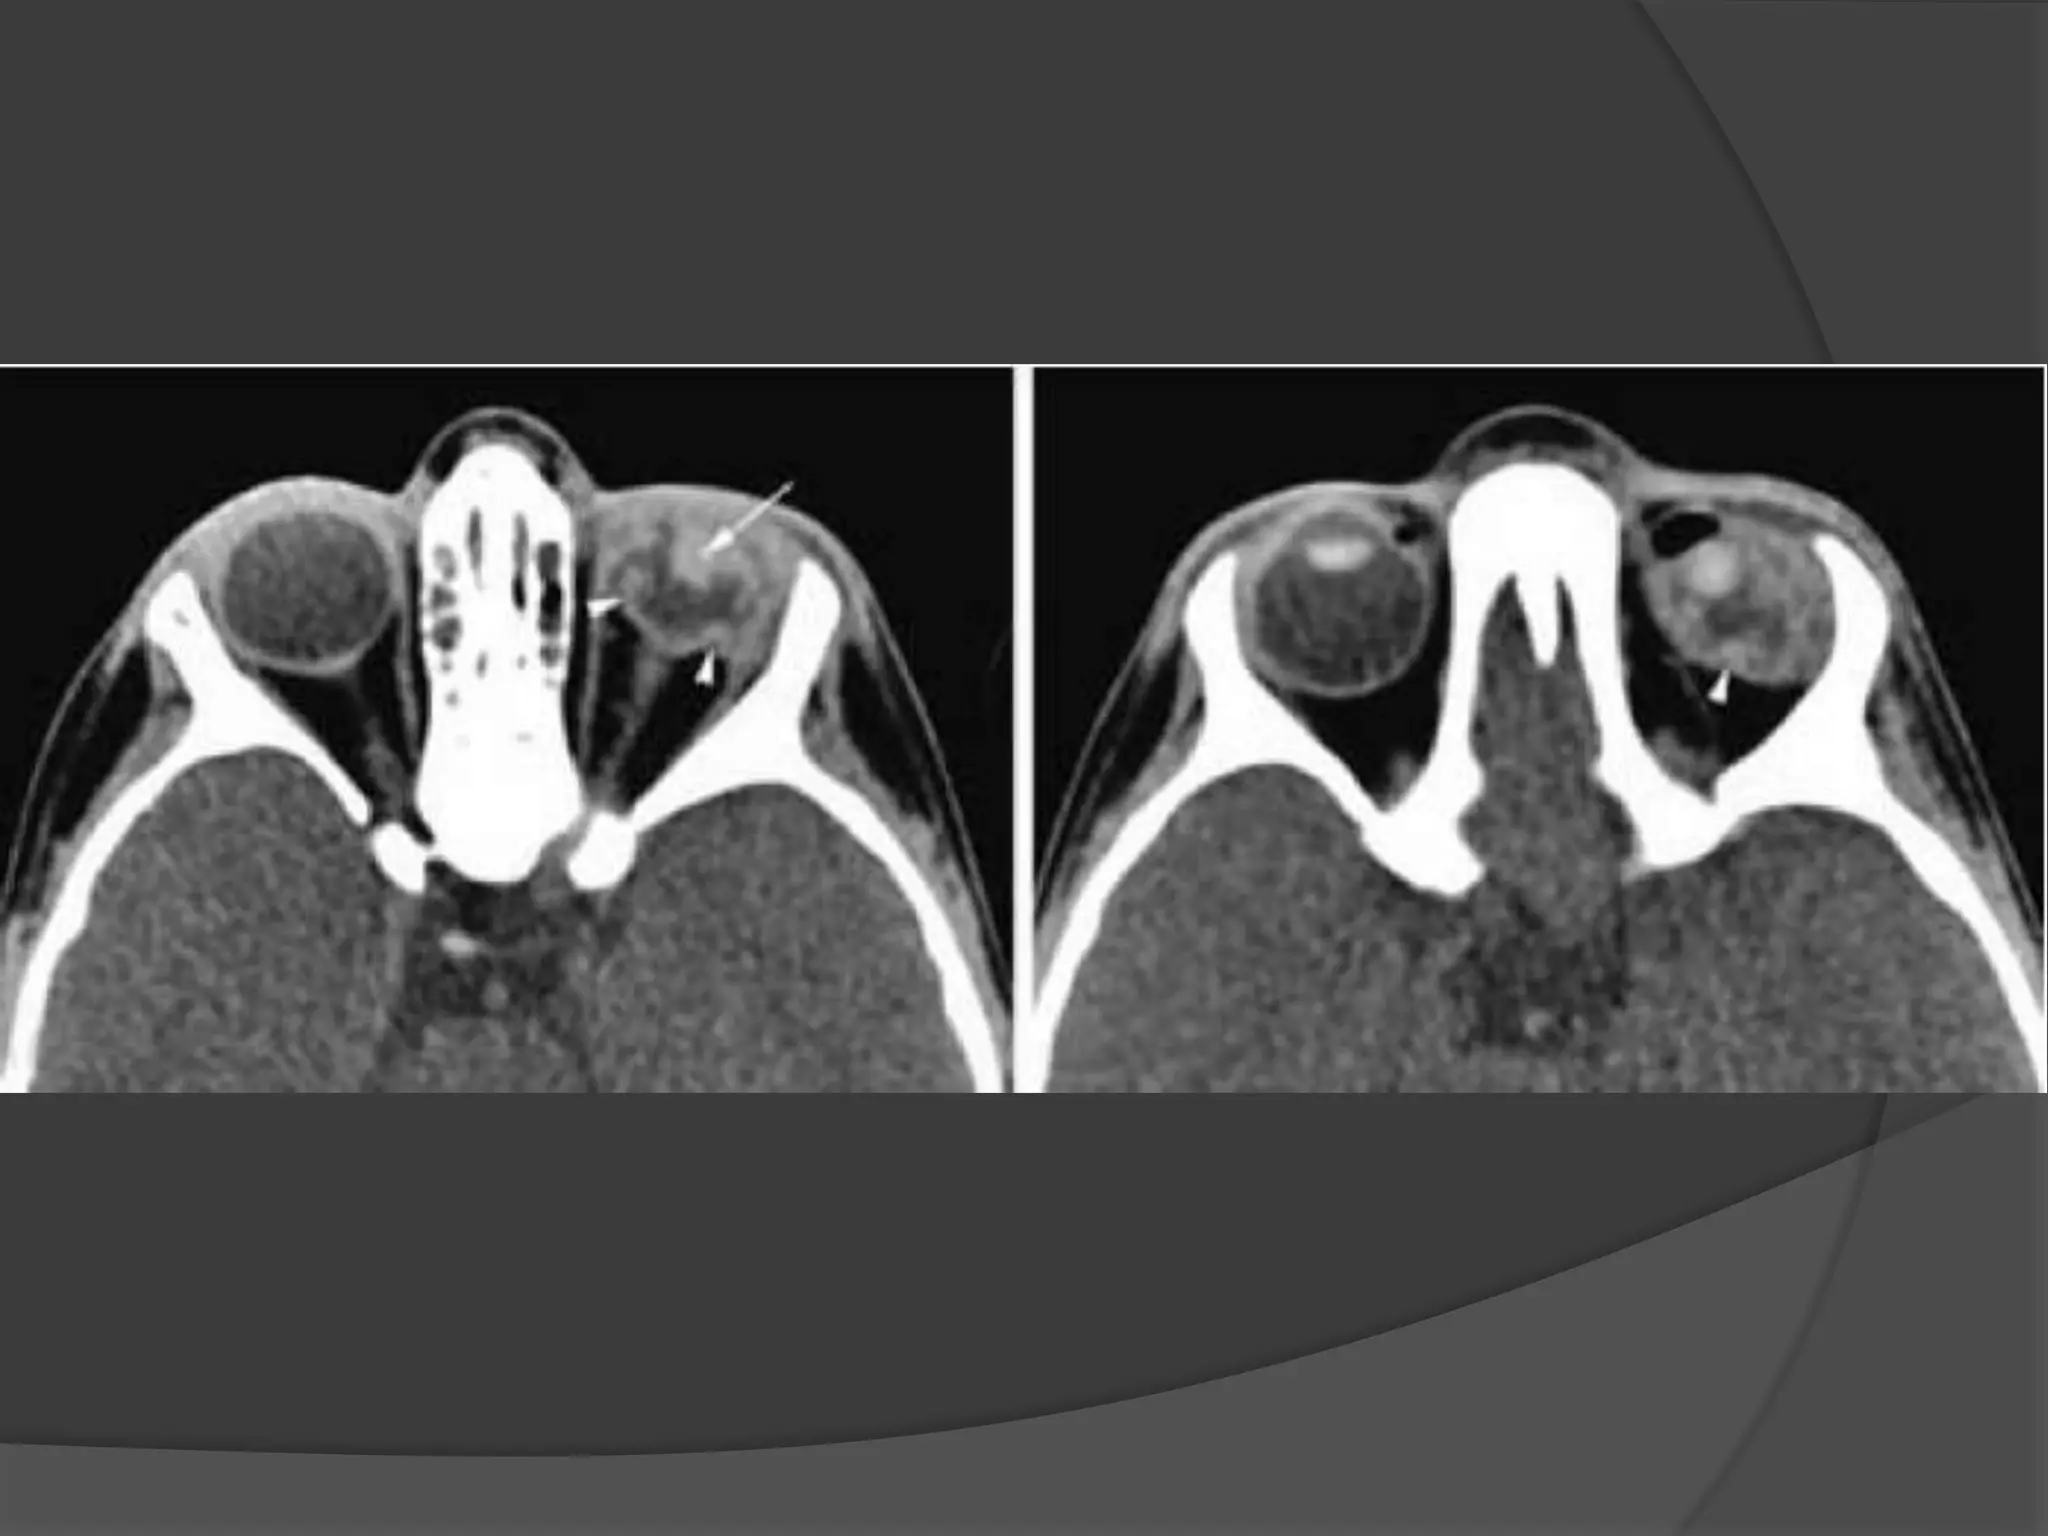

Fig A. Optic nerve Meningiomas. CT -- Enhancement of thickened right

optic nerve with elevation of optic disc (arrowhead).

Fig B. Axial T1-weighted post contrast fat-saturated image (B) demonstrates

peripheral enhancement of the thickened right optic nerve sheath.

Nonenhancing soft tissue within represents the encased optic nerve.